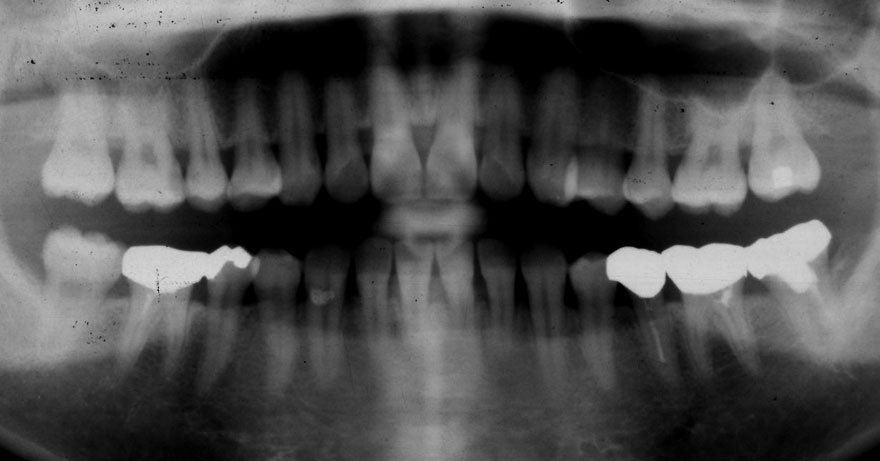

初診時 38歳 男性 平均歯槽骨喪失量:6.520mm

25年後 63歳

平均歯槽骨喪失量:8.57mm

25年間喪失量:-2.05mm

年間喪失速度:-0.08mm

(ケア頻度:1.38ヵ月ごと)